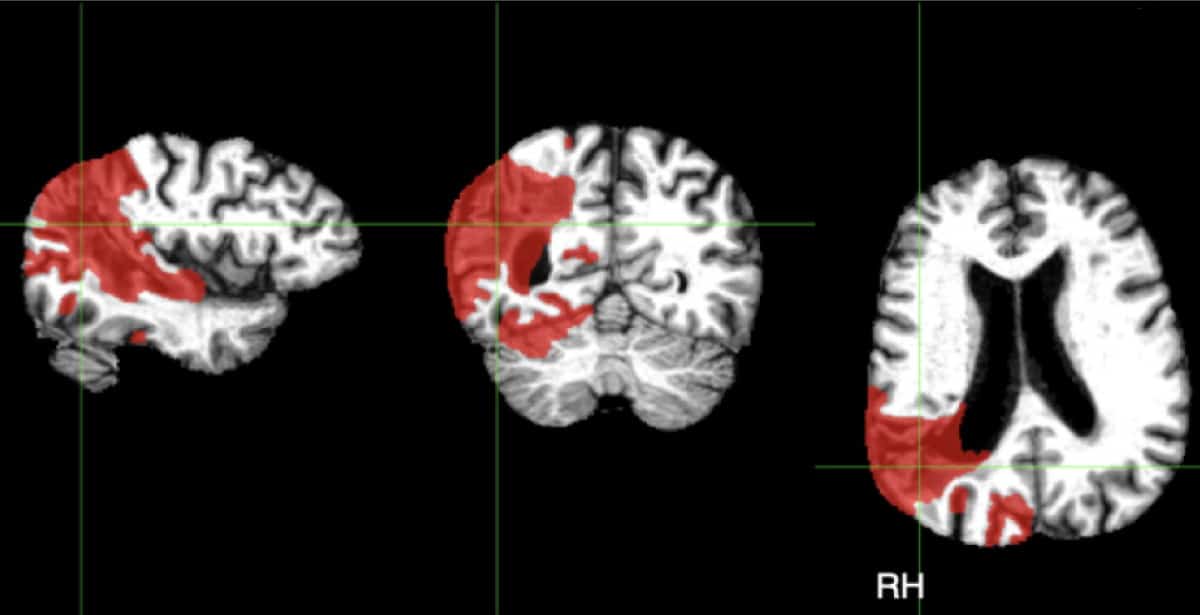

Watershed Strokes After Cardiac Surgery Stroke

From www.ahajournals.org

Watershed Strokes After Cardiac Surgery Stroke Can You See A Past Stroke On Mri A brain ct scan (also called a cranial ct scan) can show if there is damage or bleeding in the brain. A tcd may reveal signs of obstructed or re. When to see a doctor. Mri scanning is an important and accurate tool for diagnosing evidence of previous strokes. With an old stroke, tissue scarring may appear as white spots. Can You See A Past Stroke On Mri.